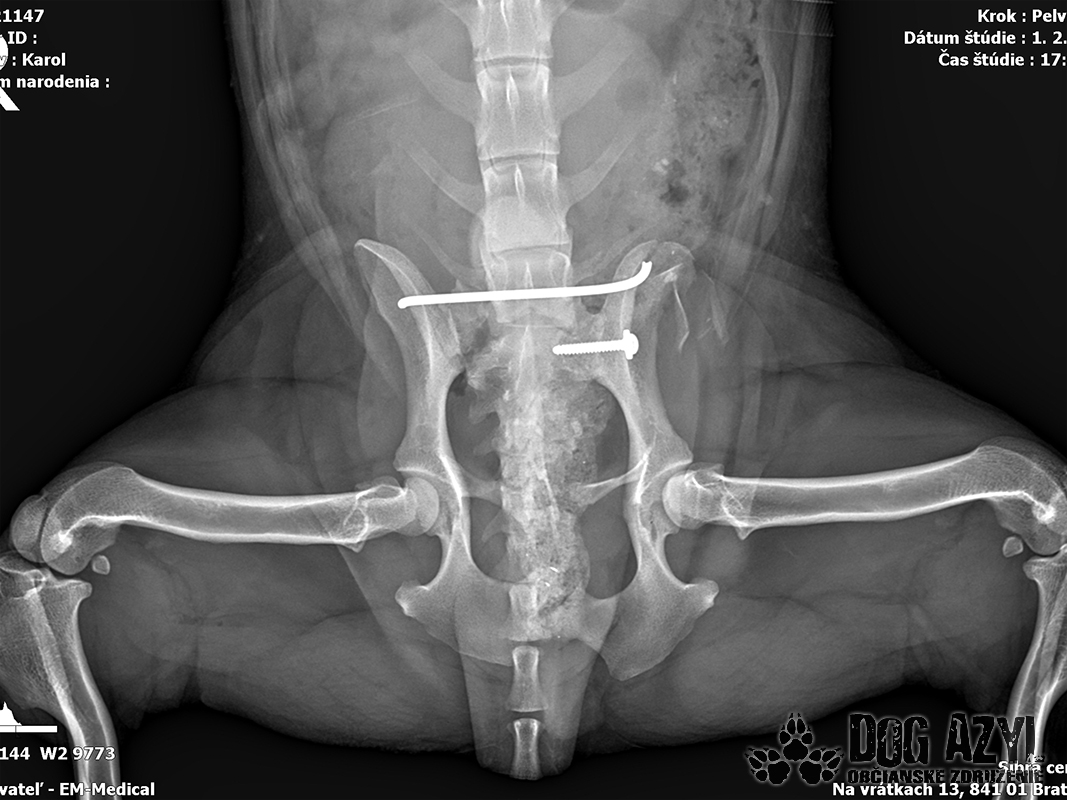

Karola nám doviezla pani, ktorá ho našla, asi jediná dobrá duša, ktorá pri ňom neprešla so zatvorenými očami. Ihneď sme s krpcom utekali na veterinu aby sa zistila závažnosť jeho zranení. Hneď pri prvých RTG snímkoch sa ukázala obojstranná fraktúra panvy, taktiež fraktúra krídla panvy a keby mu to chudákovi nestačilo, do tretice sa objavila zlomenina stavca. Karolko mal neznesiteľné bolesti, ale krásne prečkal vyšetrenie lebo vedel, že je v dobrých rukách a dostáva sa mu pomoci. Po nálezoch sme okamžite kontaktovali neurológiu a ortopédiu na veterinárnej klinike Sibra - centrum veterinárnej medicíny, kde sme dostali hneď termín na príjem.

Karol nemá žiadne neurologické deficity, po ortopedickej operácii bude vedieť behať a bez problémov bude vedieť samostatne cikať a kakať. Po tejto úžasnej správe sme samozrejme dali zelenú náročnej ortopedickej operácii pod vedením MVDr. Vatolíka. Operácia sa podarila na výbornú, Karči je "zoskrutkovaný" a vôbec nič mu nebráni v tom, aby opäť mohol behať a aktívne žiť. Momentálne sa zotavuje po operácii, musí mať prísny kľudový režim. Po vybratí stehov ho čaká hydro- a fyzioterapia, ktorá mu pomôže postaviť sa na nohy. Je to bojovník, veľmi sa chce uzdraviť a v jeho očkách je dokonale vidieť, že už kuje plány čo všetko zameškané bude musieť dobehnúť.